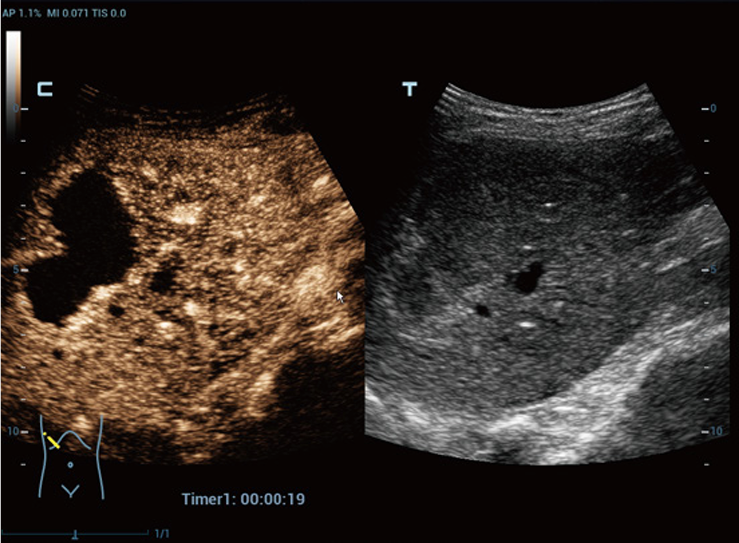

Контрастная визуализация на Mindray Resona R9 реализована с помощью технологий UWN+, Plane-Wave CEUS, Micro Flow Enhancement и HiFR CEUS. Эти режимы обеспечивают высокую частоту кадров и точное отображение микрососудистого русла. Врач получает возможность различать доброкачественные и злокачественные образования, оценивать перфузию, микроциркуляцию и характер васкуляризации.

Сравнение изображений в В-режиме и при контрастировании. Режим CEUS позволяет оценить перфузию и васкуляризацию очага, уточнить характер образования и границы поражения

Контрастная визуализация на Mindray Resona R9 реализована с помощью технологий UWN+, Plane-Wave CEUS, Micro Flow Enhancement и HiFR CEUS. Эти режимы обеспечивают высокую частоту кадров и точное отображение микрососудистого русла. Врач получает возможность различать доброкачественные и злокачественные образования, оценивать перфузию, микроциркуляцию и характер васкуляризации. Автоматизированные инструменты упрощают повседневную работу.